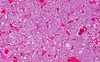

Primary CNS lymphoma (pathology)

- most commonly diffuse large B cell (approximately 3% of all primary brain tumors)

- CD20, CD19, CD79a + (normal T-cells will stain for CD3, but very small number)